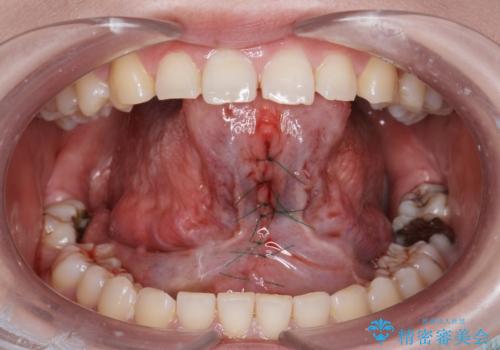

[舌小帯の形成術] 舌の動きが悪い 滑舌を改善したい!

滑舌の改善 舌小帯の形成術

- 外科手術のため、術後に出血、痛みや腫れ、違和感を伴います

- 口腔内の状態によっては適応できないことがあります